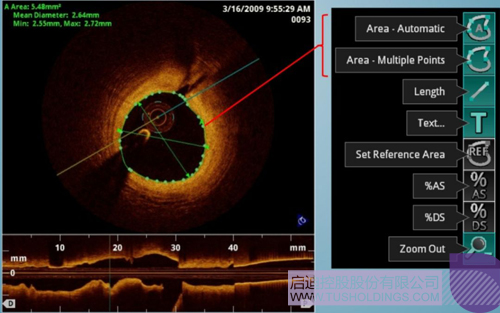

光學(xué)相干斷層成像技術(shù)(OCT)是一種新型影像技術(shù),它利用弱相干光干涉儀的基本原理,檢測(cè)生物組織不同深度層面對(duì)入射弱相干光的背向反射或幾次散射信號(hào),通過(guò)掃描,可得到生物組織二維或三維結(jié)構(gòu)圖像。OCT由于具有極高的分辨率(10 um),可以對(duì)內(nèi)膜性質(zhì)和支架結(jié)構(gòu)更加精確地辨別和分析。

在冠脈介入治療迅猛發(fā)展的今天,隨著復(fù)雜病變患者日益增多,血管內(nèi)影像扮演了越來(lái)越重要的角色。OCT借助其高分辨率的圖像優(yōu)勢(shì),可以提供更清晰的病變特征和支架植入情況,OCT存在以下優(yōu)勢(shì):可更精確的檢測(cè)介入治療后的血管內(nèi)情況,如夾層、支架貼壁不良、組織脫垂等,另外,它在管腔直徑和面積方面的測(cè)量精度更高。

血管腔內(nèi)精準(zhǔn)評(píng)估

中科微光采用的是SS-OCT技術(shù),該技術(shù)在臨床上具備顯著優(yōu)勢(shì),例如回拉速度更快、采樣幀數(shù)更多、安全性更高。同時(shí)該技術(shù)也是當(dāng)前OCT領(lǐng)域的最前沿技術(shù),中科微光將爭(zhēng)取實(shí)現(xiàn)國(guó)內(nèi)首臺(tái)內(nèi)窺OCT造影系統(tǒng)商業(yè)化,幫助醫(yī)生在手術(shù)中根據(jù)影像快速制定手術(shù)策略,幫助患者有效減少急性心梗造成的死亡等。